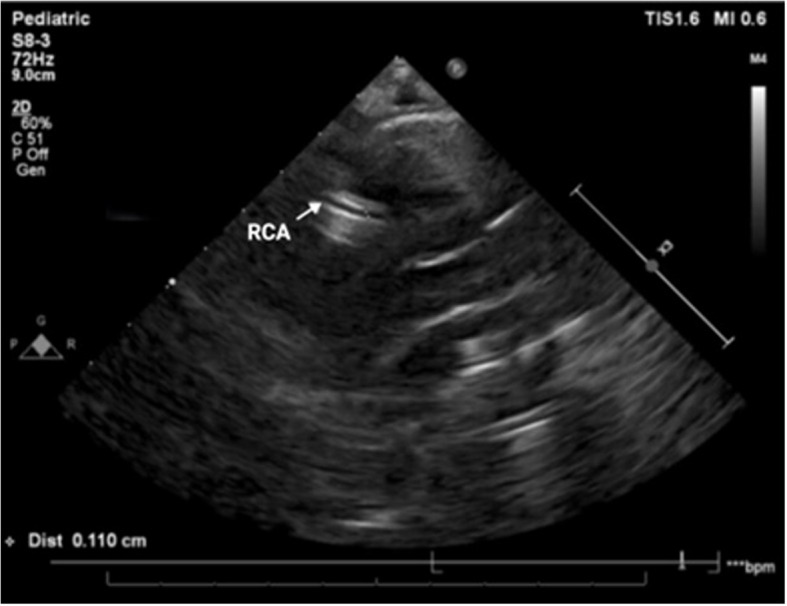

Echocardiography demonstrated normal calibre coronary arteries, with hyperechoic foci in the right coronary artery, normal myocardial contractility, and a small pericardial effusion (Fig. 5).

Fig. 5.

Case 2, echocardiogram on day 4 of admission. Parasternal short axis view, demonstrating hyperechoic walls of RCA, which is not dilated (diameter 1.66 mm; z-score 0.08). — RCA (right coronary artery)